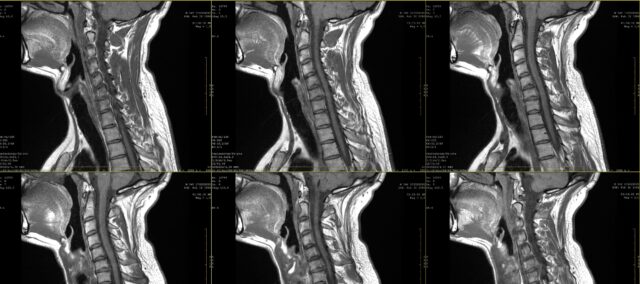

Do této studie byli zařazeni účastníci s dvouměsíční anamnézou přetrvávající bolesti, u nichž byla na MRI diagnostikována cervikální radikulopatie, aby se zjistila shoda mezi kresbami radikulární bolesti a nálezy na MRI. Tuto diagnózu stanovil neurochirurg na základě klinických informací a nálezů na MRI hodnocených radiologem.

Ve škole jste se jistě učili o kreslení bolesti při radikulární bolesti. Již v prvním desetiletí 21. století se však ukázalo, že radikulární bolest nemusí mít nutně dermatomální distribuci. Cílem této studie bylo blíže se podívat na shodu mezi vizuální kontrolou kreseb radikulární bolesti, jak ji zaznamenali pacienti, a magnetickou rezonancí. V praxi se často stává, že pacient vyjádří své stížnosti a ty mohou být doplněny kresbou bolesti. Při podezření na radikulární bolest se často předepisuje lékařské zobrazovací vyšetření, aby se určil postižený nervový kořen a rozsah možného postižení nervového kořene. Přestože je to v mnoha případech součástí rutinní praxe, nevíme, dokud neznáme shodu mezi těmito kresbami bolesti a postiženým nervovým kořenem určeným pomocí MRI. V této studii Marco et al. (2023) porovnávali nákresy radikulární bolesti a nálezy na MRI.